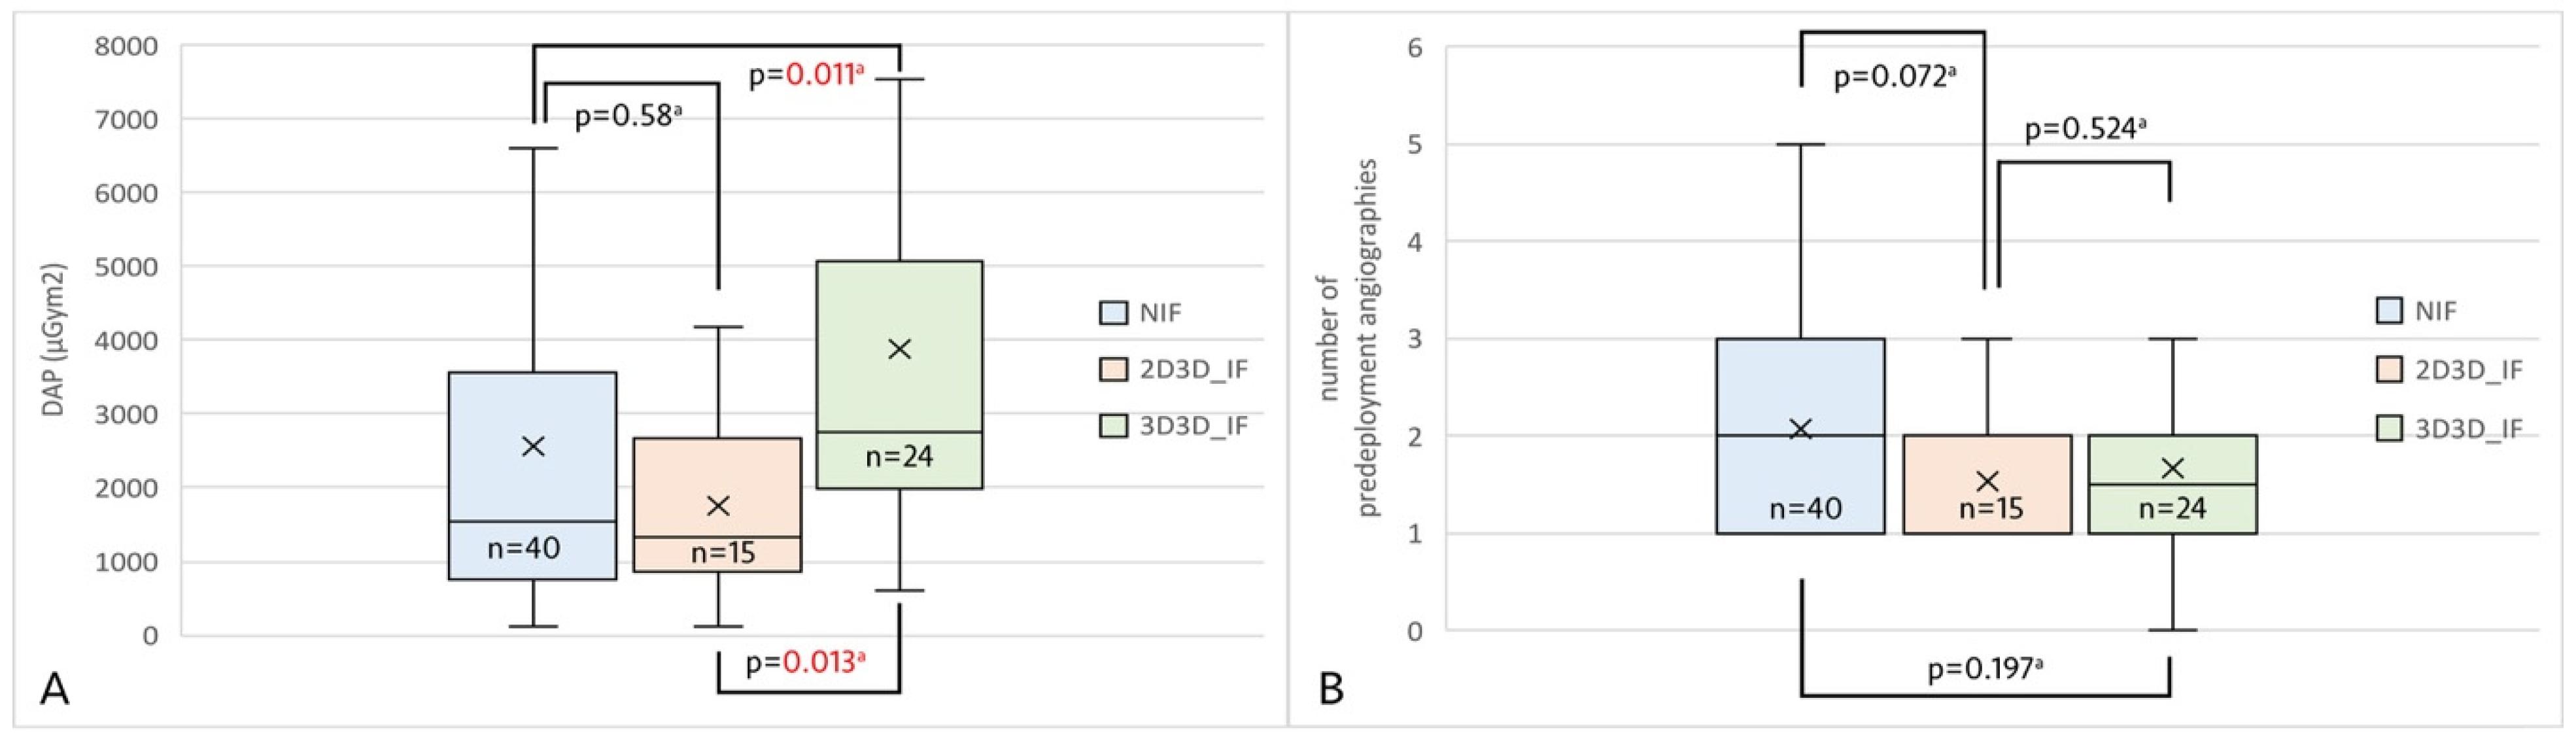

3. Results

Z3 TEVAR Subgroup